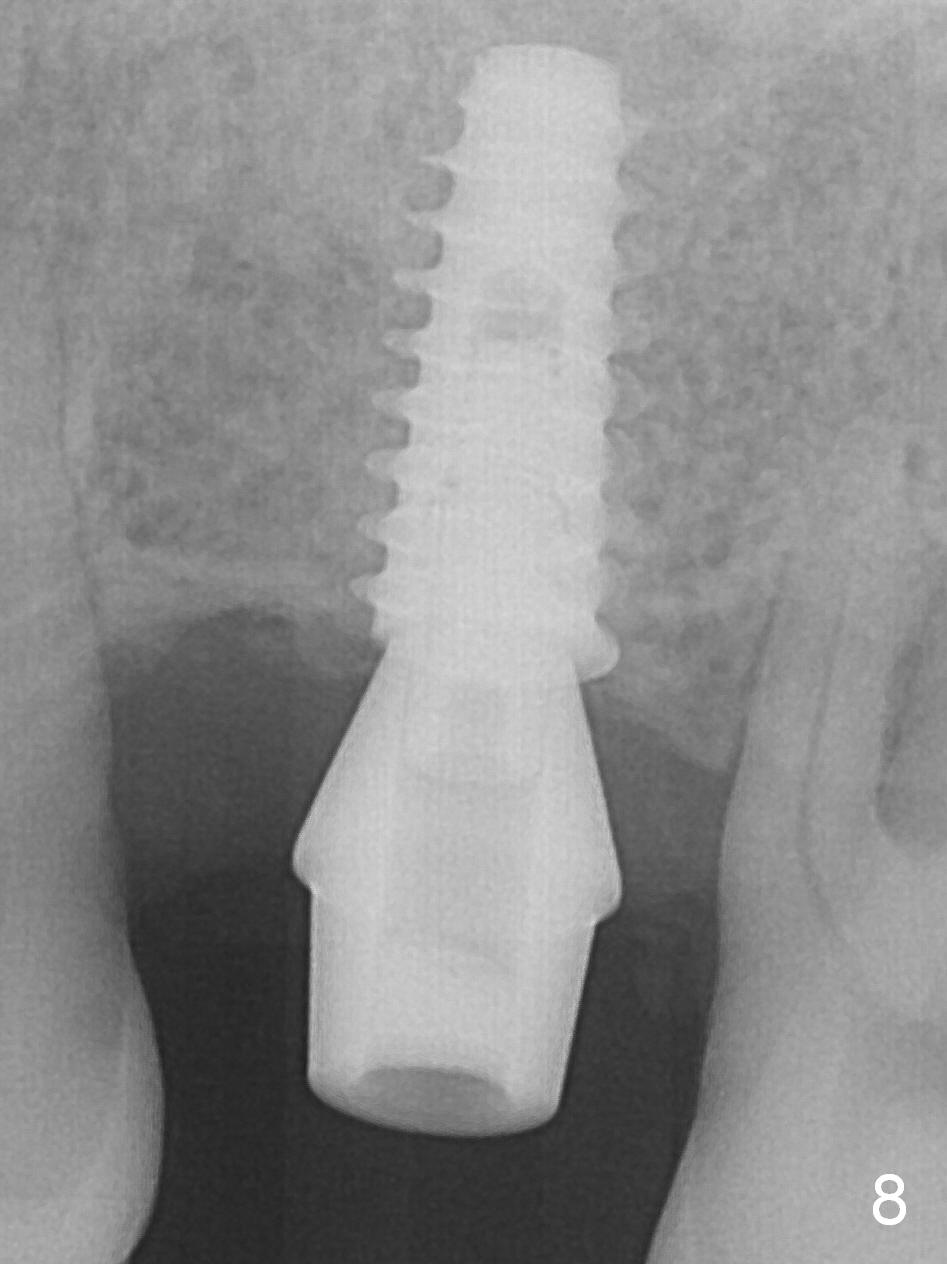

Magic split is designed to test bone density after incision (Fig.1). Since it is sharp and blade-shaped (Fig.2), it is used as a scalpel to penetrate the mucosa at the crest of #14 and tapped in for ~ 7 mm from the gingival margin. The bone density is moderate. Osteotomy is initiated with 1.6 mm pilot drill for 13 mm (Fig.3,4 (red line: the lower border of the sinus floor) and increased by Magic Expanders (ME) and Magic Drills until 4.5x13 mm. A 5x11 mm dummy implant is placed (Fig.5). After reusing ME 3.8 mm for 13 mm at the palatal gingival margin (which is more apical than the buccal one by ~2 mm), a definitive IBS implant (5x11 mm) is placed (Fig.6). Later the implant is turned 4 more times. Without an incision, there is no hemorrhage when a 6x4(4) mm Hexa abutment is placed (Fig.7 (palatal view) A). As a routine, an immediate provisional is fabricated with occlusal clearance. The implant/crown ratio is less favorable. Restore more than 4 months. In fact, the patient returns for crown 4 months postop. The implant appears to have osteointegrated (Fig.8).